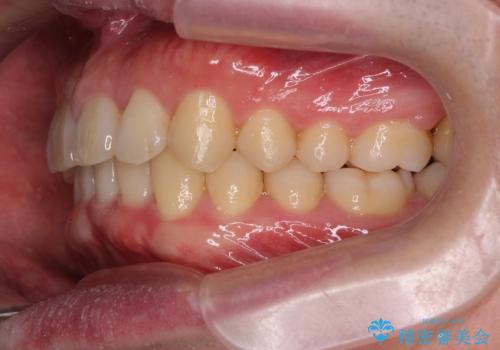

下の歯のがたつきが気になる。 インビザラン&ワイヤー部分矯正併用

- 下の歯が気になるとの事で来院。

左上の奥歯がシザーバイトがありワイヤーで部分的な矯正を行い、シザーバイトを改善した後にインビザラインで全体的な矯正治療を行いました。

シザーバイトは歯と歯が噛み合っていないのでしっかり噛むように処置をする必要があります。

歯のがたつきが改善され大変満足されました。